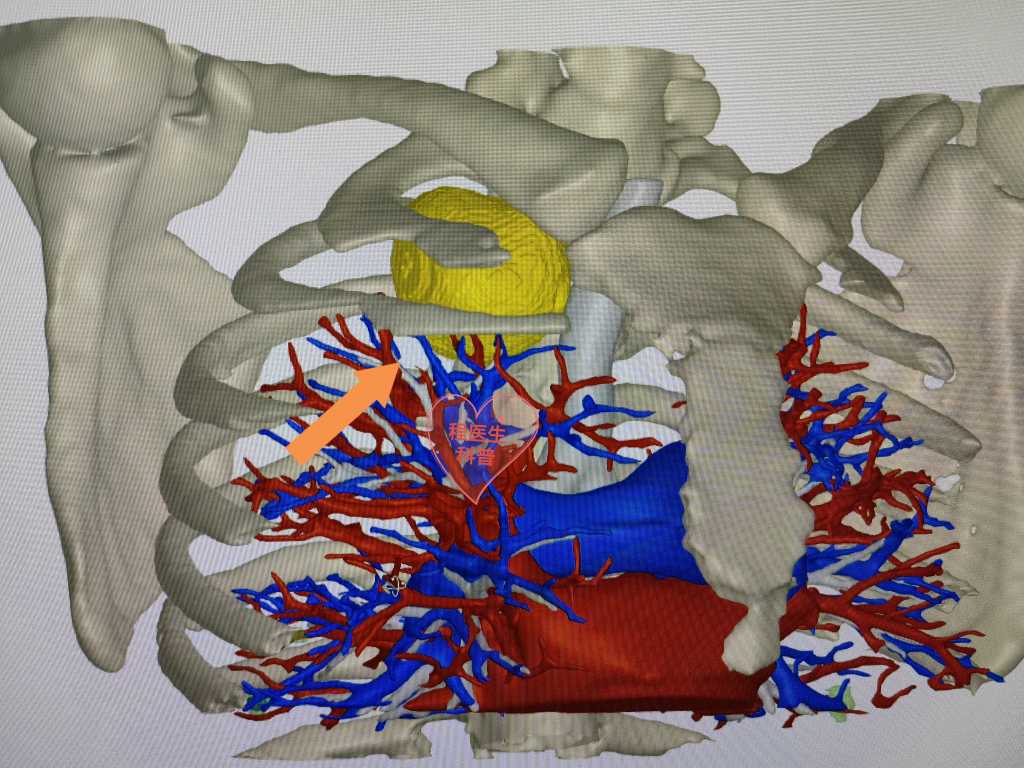

通过胸部CT检查我们发现,秦大姐的肿瘤在一个关键的“交通要道”:大部分在胸腔,还有一小部分在颈部!此处既是神经的重要“聚集地”,也是血管进出上肢和头颈的必经之路,肿瘤继续生长可压迫血管、神经引起一系列并发症,严重者可能导致脑水肿、上肢功能障碍、视力障碍等问题,因此我们建议秦大姐早点手术治疗。

“需要切多大的口子,能不能快点出院?……”针对秦大姐对手术治疗的担心,我们做了充分的准备,设计了手术方案和备用方案:首选创伤最小的单孔胸腔镜手术,若肿瘤与颈部血管粘连作颈部辅助小切口,备开胸手术。通过与秦大姐多次沟通疾病特点和手术方式,她的疑虑终于打消,选择积极手术治疗。

术中我们发现,秦大姐的肿瘤紧贴血管、神经,只要有丝毫的损伤都会引起大出血或神经功能受损。手术过程中,我们小心翼翼分离粘连,切开纵隔胸膜、游离血管神经、分离肿瘤,终于顺利切除肿瘤,用时仅1小时,手术切口不到4公分,病检结果证实为神经鞘瘤。术后秦大姐未出现任何并发症,在医护人员和家属的精心照护下,手术后1天多时间就康复出院了。